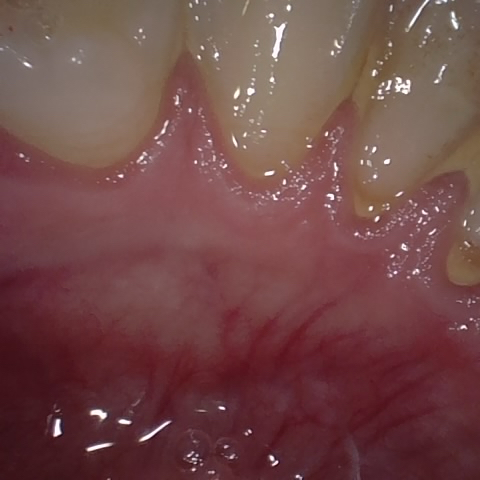

Annotated as "Good"